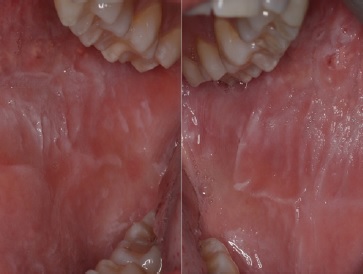

Intraoral examination revealed white corrugated bilateral lesions on the buccal mucosa that extended beyond the occlusal plane (Figure 1). Although there was mild sloughing on the most prominent lesions, they were not removable by scraping.

Figure 1 Intraoral presentation of the lesions, showing the white diffuse corrugated, spongy plaques and their extension on the right and left buccal mucosae.

There were no similar lesions elsewhere in the remaining oral mucosa. Given the patient´s age and no known history of trauma, the clinical presentation, and the lesions’ bilateral nature, we presumed a WSN diagnosis.